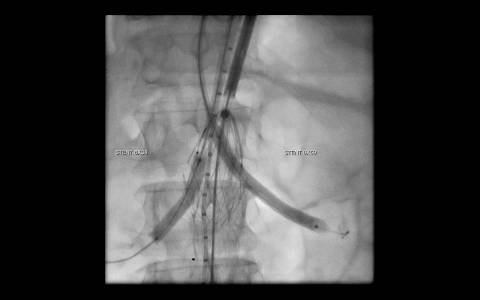

A avaliação por tomografia computadorizada evidenciou um aneurisma infra-renal de colo hostil e acessos vasculares com muita ateromatose. Diante do contexto clínico e de imagem foi optado pelo tratamento endovascular com endoprótese de baixo perfil Incraft CORDIS e técnica de Snorkel Grafts com stents Palmaz CORDIS para as artérias renais.